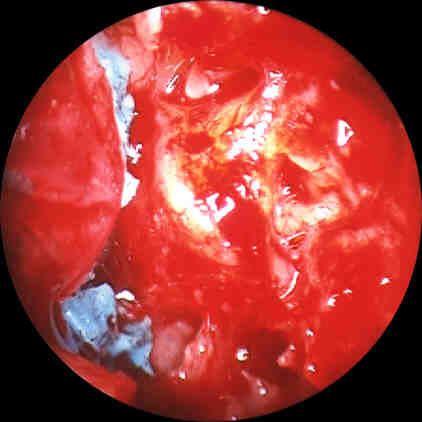

Figure 3. Initial surgical exposure shows residual impression material in the operative field. Click image for full size view.

It was initially felt visually that the incudostapedial complex was encased

in silicon. As the silicon was retracted inferiorly from this area, however, it

was seen that the silicon extended to/and abutted against the incudostapedial

complex but did not surround and encase the ossicles. The ossicular chain was

therefore able to be kept intact throughout the procedure. All posterior and

inferior areas of the tympanum were able to be cleaned of the silicon using

this piecemeal removal. At this point additional photographs (Figures 4-6) were taken.